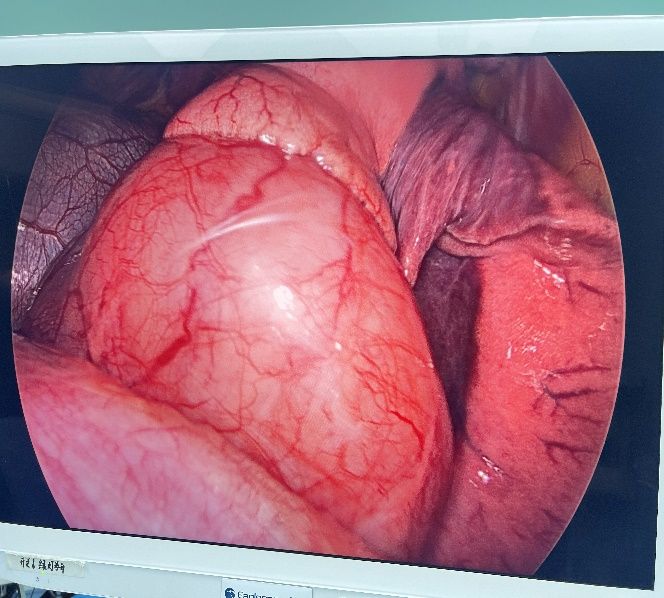

在2024年10月21 日,姜建涛主任医师、李建忠副主任、赵丹文医师为小张实施了手术治疗,术中先尝试胸腔镜手术,腔镜下可见食管下段至贲门巨大隆起性病变,姜主任评估后认为腔镜下操作困难大,遂将操作孔延长至5cm行手术,术中发现肿瘤环食管周生长,完整剥除及其困难,但考虑小张年轻,未避免切除食管而对小张以后的生活造成影响,姜主任团队仔细操作,尽可能为小张保住食管,在姜主任及其团队的精心操作下,手术顺利,手术仅历时一个多小时,便将肿瘤完整剥除,剥除下来的肿瘤长径达到了快13cm,试水检查食管粘膜未损伤。在术后第一天查房的时候小张已经能下地活动了,激动的拉着姜主任的手,感谢姜主任为她成功实施手术并保住了食管,感叹姜主任的高超技艺,现小张一切恢复顺利,已康复出院。